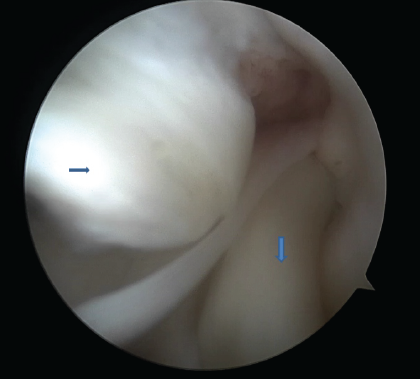

The medial fragment was displaced into the intercondylar notch; the lateral tear extended into the anterior horn. There was no tunnel widening. The reconstructed ACL graft appeared to be intact. However, the femoral tunnel is more vertical, indicating the trans-tibial technique for the graft placement. Arthroscopy was performed under spinal anesthesia with the patient in the supine position and under tourniquet. Standard anterolateral and anteromedial portals were used. During the first view of diagnostic arthroscopy, the displaced medial and lateral meniscus bucket-handle fragments with the intact ACL were visualized (Fig. 2). No cartilage changes were encountered.

Figure 2: Displaced both meniscus bucket handle tear in the center of the knee joint (right pointing arrow – displaced medial meniscus bucket handle tear, down arrow – displaced lateral meniscus bucket handle tear.